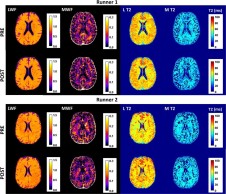

In the study carried out by the University of the Basque Country, the brains of several marathon runners were scanned and it was observed that, after the race, the brain's myelin had significantly reduced, clear evidence that it had been used by the brain as fuel in the absence of glucose. After two weeks, the runners' myelin levels began to normalize.